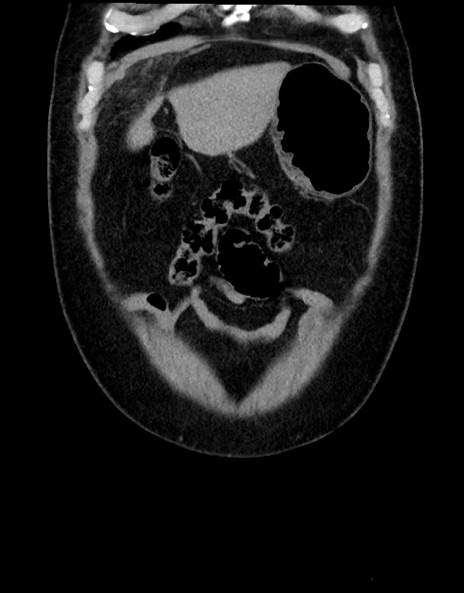

症例15(冠状断像)

横断像